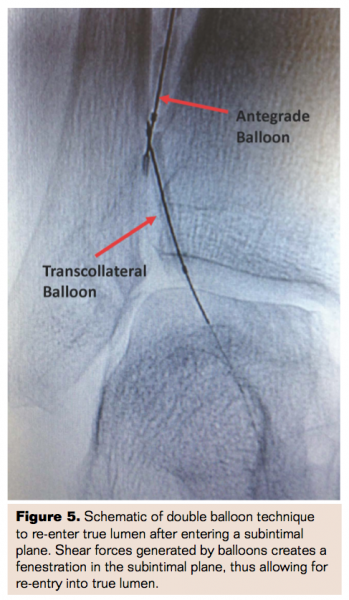

Antegrade and Retrograde Wires Enter Subintimal Planes

If the antegrade wire followed by the retrograde transcollateral wire enters two different subintimal planes, a double balloon technique can be used to fenestrate the two lumens of the vessel (Figure 5). To do this, both antegrade and retrograde wires are advanced using multiple angiographic views to ensure that the wires are no more 2-3 mm apart.9 PTA balloons are advanced over each wire, abutting the tips of the balloons. Both balloons are inflated simultaneously, successfully fenestrating the lumen at the tips of the balloon.10 The antegrade wire is then advanced into the retrograde channel and distally into true lumen. The retrograde equipment is then removed and the vessel is treated from an antegrade fashion.